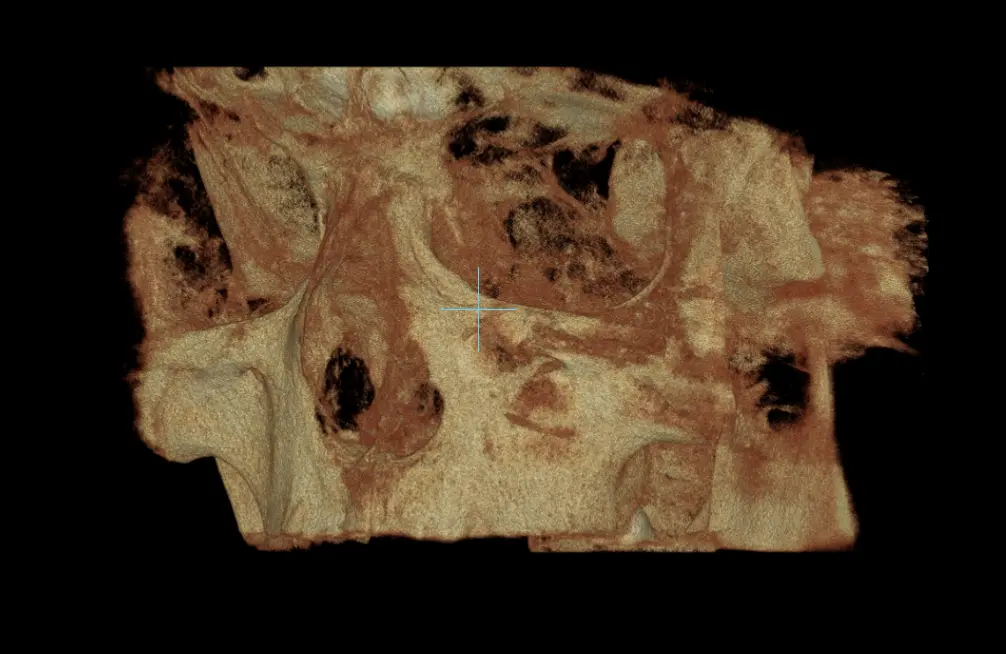

TOMOGRAFÍA PARA PLANIFICACIÓN DE MARPE

Evalua el estadio de la sutura intermaxilar y condiciones óseas del hueso palatino.